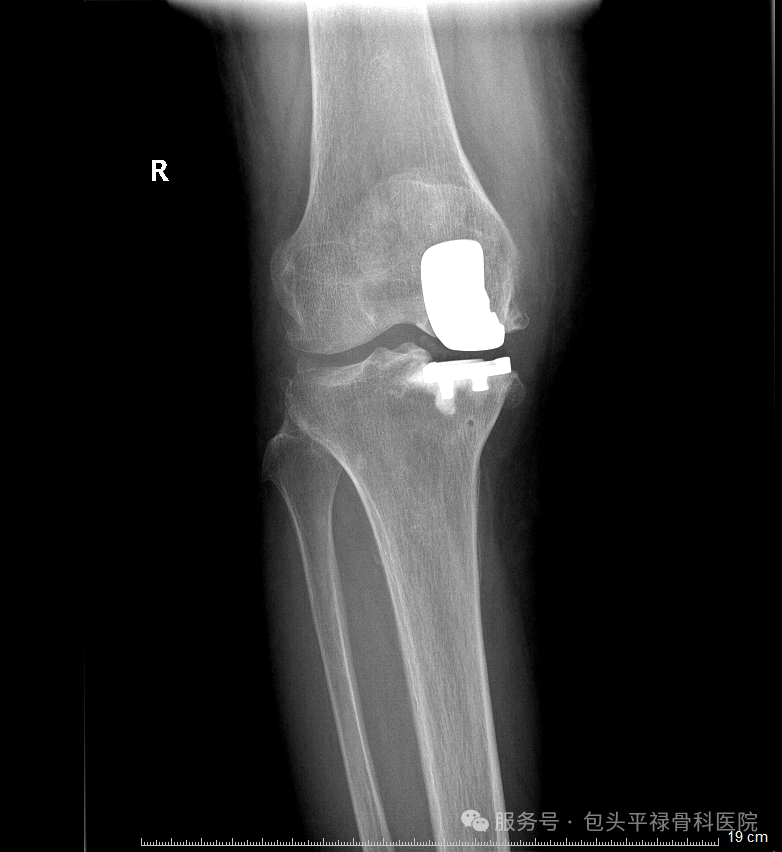

以单髁置换术为例:只换掉膝盖里磨损严重的房间“地板”,保留健康的墙壁、承重梁和隔壁房间。

1.这不仅仅是“少换一点”那么简单,它意味着:

2.创伤更小:切口更短,切除的骨头更少,出血少

3.恢复更快:术后当天或第二天就能下地,大多数患者术后一到三个月即可逐步回归日常生活

4.感觉更自然:保留原膝所有重要的韧带,运动时的本体感觉几乎和原来一样

5.未来选择更多:即使若干年后保膝手术的效果减退,仍然可以考虑进行全膝关节置换,比全膝置换的翻修要简单得多